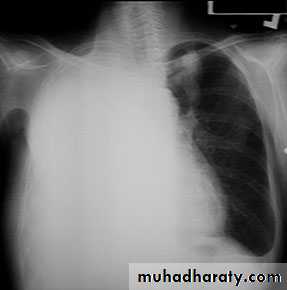

Complete rt. & left Lung collapse